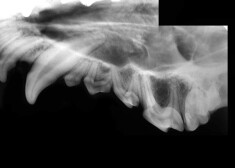

Kā izrādās, smaganu slimības ir visbiežākās injfekcijas slimības pieaugušiem suņiem. Tāpat kā cilvēka, arī suņa mutē pēc ēšanas paliek pārpalikumi, kas, sajaucoties ar siekalām, sāk veidot aplikumu uz zobiem. Ja šis aplikums netiek laikus notīrīts, tas pamazām sacietē un veidojas zobakmens, bet suņa mutē uz dzīvi apmetas īsts baktēriju midzenis. Baktērijas uzbrūk suņa smaganām, ar laiku radot nopietnus bojājumus. Viss sākas ar smaganu iekaisumu, kas no to virskārtas plešas arvien dziļāk. Galu galā tiek skarti zobus saturošie audi un sunim gluži vienkārši sāk izkrist zobi, bet iekaisušās smaganas sagādā neciešamas sāpes. Vaļīgi zobi, to trūkums, iekaisušas smaganas - tas viss sunim sagādā ciešanas katru dienu. Suņa dzīves kvalitāte būtiski samazinās. Suns kļūst nelaimīgs, tādēļ mainās arī viņa raksturs, kas savukārt var sagādāt vilšanos saimniekiem.

Pētījumi pierāda, ka tieši mutes dobuma problēmas var novest pie sirds slimībām un samazināt mājas mīluļa dzīves ilgumu. Baktērijas, kas rodas suņa mutē, caur bojātajām smaganām nonāk suņa asinsritē un ceļo pa visu organismu. Tās var sasniegt sirdi un inficēt to. Jo īpaši bīstami tas ir kucēniem un mazo šķirņu suņiem, kuru ķermenis ir fiziski vājāks, bet asinsrites loks mazāks, tādēļ infekcijas izplatās daudz straujāk.